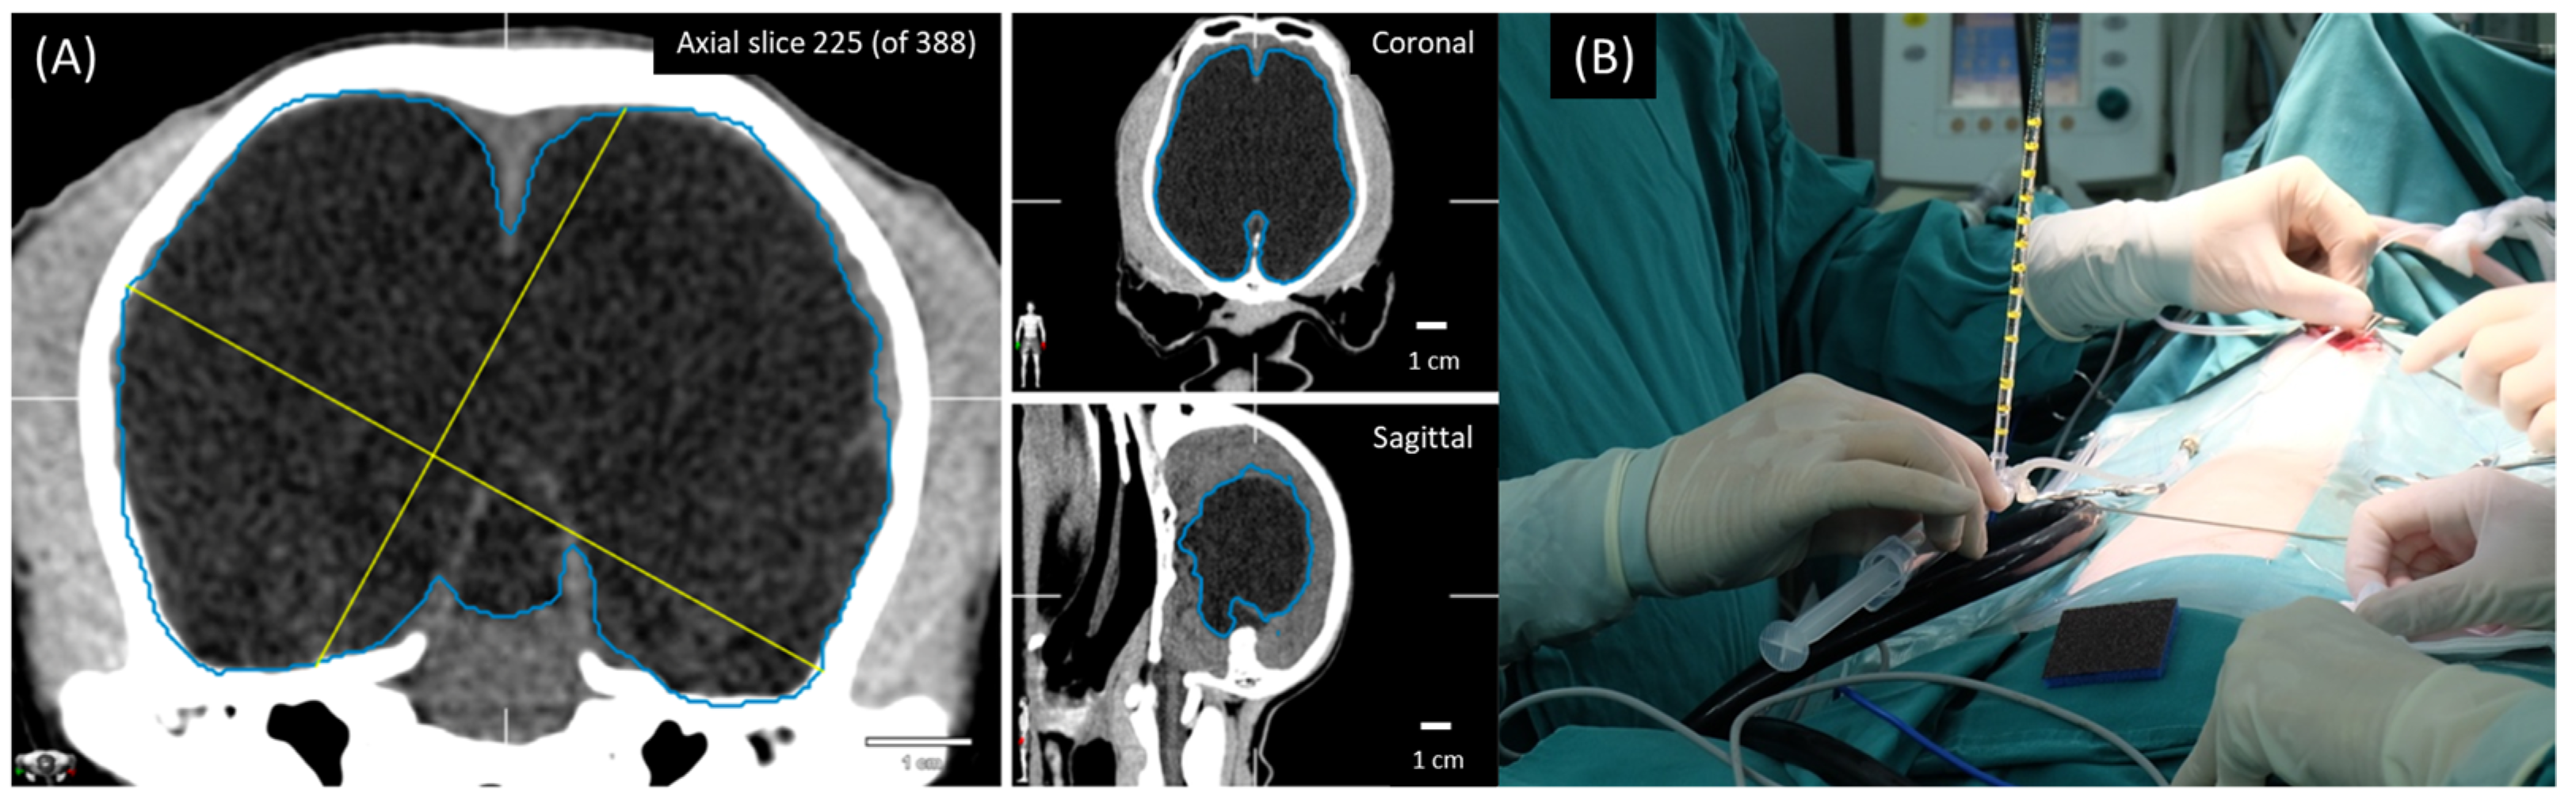

2.1. Treatment